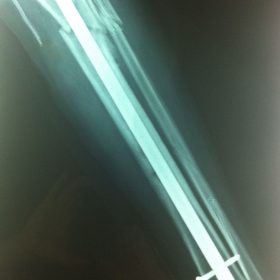

Κατάγματα Μηριαίου ή Κνήμης

Τα κατάγματα της Διάφυσης των οστών της κνήμης και του Μηριαίου οστού στη σύγχρονη ΟΡΘΡΟΠΑΙΔΙΚΗ αντιμετωπίζονται με ΕΝΔΟΜΥΕΛΙΚΗ ΗΛΩΣΗ.

Δύο τομές 3 εκατοστών και 1 εκατοστού αντιστοίχως για την εισαγωγή και το κλείδωμα του ήλου μέσα στο οστό. Η μέθοδος είναι κλειστή,σχεδόν αναίμακτη,διάρκειας 60 λεπτών,με τη βοήθεια C-ARM (τηλεόρασης).